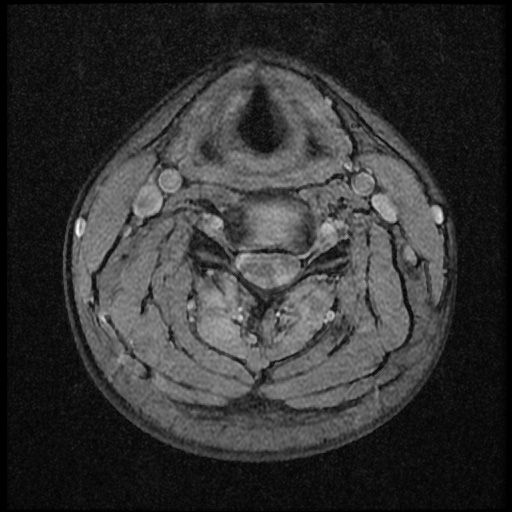

이 MRI 사진은 21년도 사고 당시 찍은 MRI 사진 입니다. 확인 부탁드립니다~

전체 mri를 다 봐여겠지만 보여주신 mri 컷에서는 의미있는 경추 디스크탈출이 보이지 않습니다.